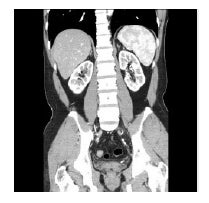

◇Ai写真も豊富に掲載!

遺体を傷つけずに調べることができるAi(オートプシー・イメージング)の写真を多用し、リアルなカラダを見ることができます。